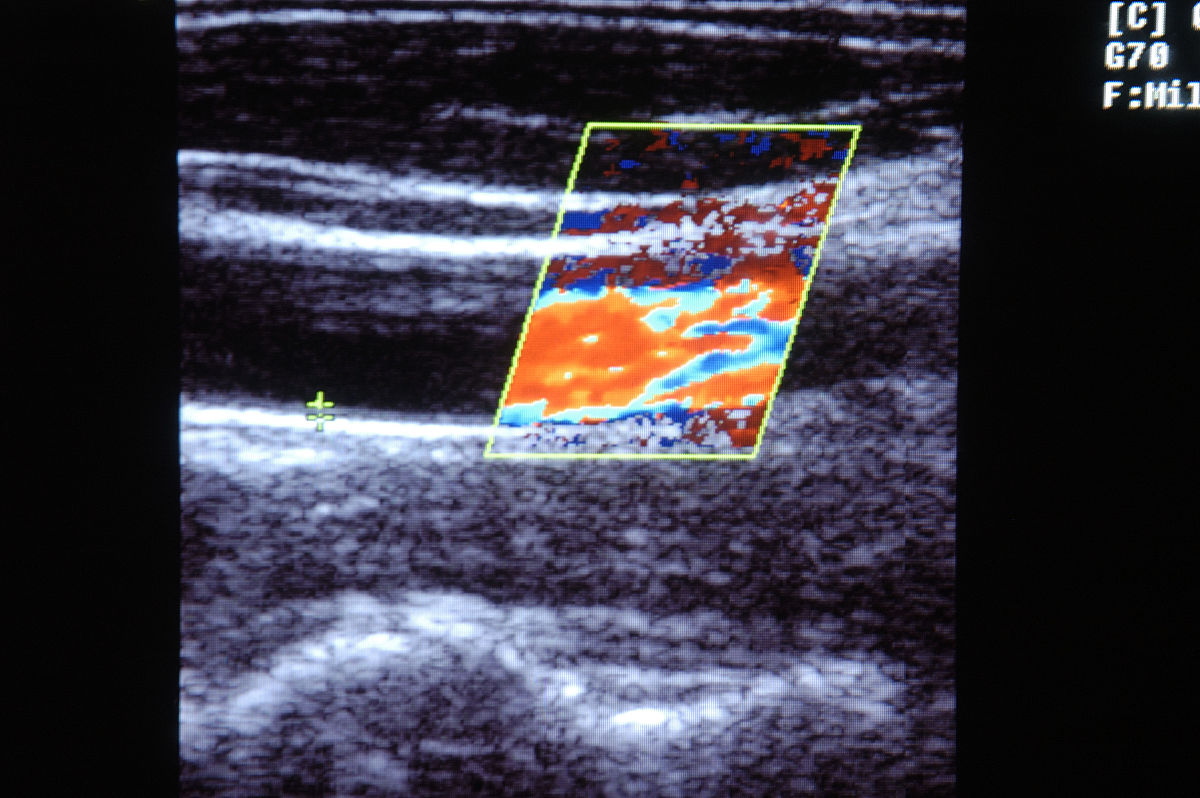

我们的荟萃分析包括了六项比较研究,报告了ACR CEUS LI-RADS算法和改良CEUS LI-RADS算法在使用Sonazoid作为造影剂时的诊断性能的直接对照比较。将本荟萃分析的范围限制在个体内两两比较中有助于减少仪器类型和操作者引起的潜在偏差,并提供了更高水平的证据。汇总数据的结果表明,改良的LR-5算法的诊断敏感性较ACR LR-5算法更高(P<0.05),然而,两种LI-RADS算法的总体诊断性能(汇总AUC)相当,尽管改良的LR-5算法的值更高(0.879和0.845,p>0.05)。 Sonazoid是一种第二代造影剂,于2007年首次在日本上市,并在其他5个国家获得了批准[11],具有与其他造影剂不同的理化特性。Sonazoid的微泡可以被库普弗细胞吞噬,并在肝实质中积聚,因此Sonazoid的造影增强相可以分为两个主要阶段——血管相和库普弗相。血管相包括动脉相(注射后15到45秒)、门脉相(注射后45秒到1分钟)和血管-库普弗相(注射后1到10分钟),库普弗相被定义为注射后10分钟[12]。随着Sonazoid在临床实践中的逐渐应用,Sonazoid的CEUS LI-RADS算法引起了关注,目前文献中报告了两种主要类型的基于Sonazoid的LI-RADS算法。一种是将ACR CEUS LI-RADS算法应用于Sonazoid,另一种是改良的CEUS LI-RADS算法。 为了提高HCC的诊断准确性和规范报告,ACR在2016年开发了CEUS LI-RADS,并在2017年进行了更新。与CT/MRI LI-RADS类似,CEUS LI-RADS算法将HCC的风险分为LR-1(明确良性)到LR-5(明确HCC)的不同级别,非HCC恶性病变被归类为LR-M类。然而,当前版本的CEUS LI-RADS仅推荐纯血池型造影剂如SonoVue使用,Sonazoid未包含在最新版本的ACR CEUS LI-RADS中。近年来,随着Sonazoid的上市和逐渐应用于临床实践,一些研究显示SonoVue和Sonazoid的诊断准确性相当,也有研究表明Sonazoid甚至比SonoVue具有更好的诊断准确性。同时,也在探索将ACR CEUS LI-RADS算法应用于Sonazoid的可能性。LR-5类别被设定为专门诊断HCC,诊断标准着重于后期的轻度洗出表现。 到目前为止,已经有三个改良版Sonazoid LI-RADS。第一个简化版本的改良LI-RADS是由Sugimoto等人于2020年提出的,将KP缺损作为ACR LR-5轻度和晚期洗出的替代措施。该简化版本的其他标准与ACR CEUS LI-RADS基本相似。Hwang等人于2022年提出了下一个版本的改良LI-RADS,HCC诊断的标准是动脉相高增强(APHE)和KP缺损,与Sugimoto等人提出的简化版本一致。李等人于2022年报道了对ACR版本进行了两个修改的改良LI-RADS的第三个版本。LR-5标准的第一个修改是至少测量1cm、无边缘APHE、无洗出且具有KP缺损的病变,与上述两个版本类似。第二个修改是将至少测量1cm、无边缘APHE、早期洗出和轻度KP缺损的病变分类为LR-5而不是LR-M,提供了新的视角。最近发表的一篇综述总结和详细阐述了这三个版本的改良CEUS LI-RADS,但他们没有进行数据整合分析来评估诊断效果。 ACR CEUS LI-RADS侧重于后期特征,而改良CEUS LI-RADS利用库普弗相特征作为主要成像特征。Sonazoid LR-5和改良LR-5的汇总敏感性、汇总特异性和汇总AUC分别为0.70和0.79、0.86和0.83、0.845和0.879。在筛选文章和提取数据的过程中,有两点需要指出。首先,有两项由同一位韩国作者进行的研究都被纳入了分析。原因如下:一项是单中心研究,患者纳入时间为三年,另一项是三中心研究,纳入时间为八年;另一方面,它们的纳入条件不同,因此我们认为两篇文章之间的重复部分很小,尽管它们的纳入时间有部分重叠,但都被纳入了分析。另一个需要注意的是,李等人在他们的文章中对ACR CEUS LI-RADS进行了两个修改,两个标准的数据都是完整的,可以提取进行分析。为了统一参与的6项研究中改良CEUS LI-RADS的标准,选择了与其余5项研究一致的第一个修改的数据进行分析。 本荟萃分析存在一些局限性。首先,本荟萃分析中的改良CEUS LI-RADS算法版本略有差异,如前文所述。其次,HCC的诊断性能的异质性无法通过荟萃回归和敏感性分析很好地解释。第三,由于有关LR-4/5和LR-M类别的文章数据有限,无法进行进一步的分析,我们只是将数据汇总作为参考。第四,所有参与的研究均为回顾性研究,并且在亚洲地区进行。这可能是由于Sonazoid的批准区域的限制,需要进一步的研究来减少人口统计学和地区因素的影响并验证结果。 总之,在这项直接对照的荟萃分析中,改良的LR-5算法的汇总诊断敏感性显著高于使用Sonazoid的ACR LR-5算法,而两种LR-5算法的总体诊断性能相当。需要更多的临床数据来进一步探索